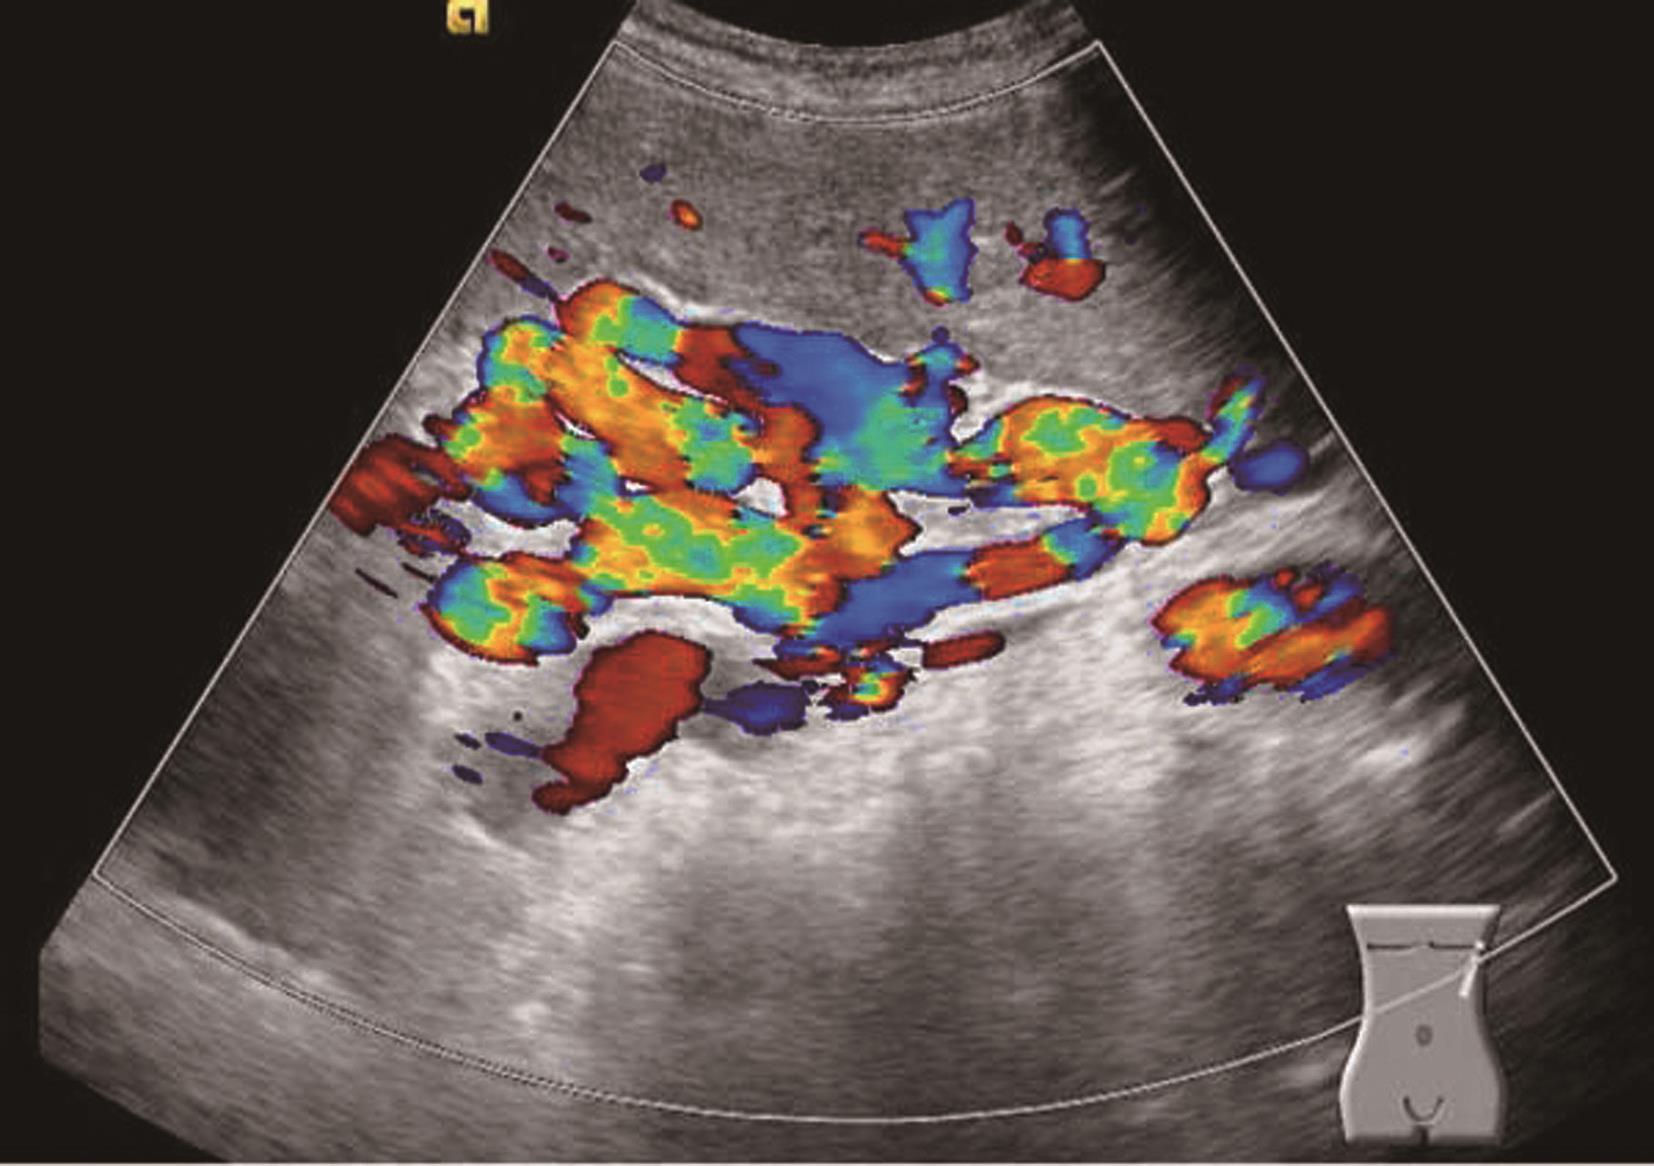

先天性肝血管畸形较为罕见,其导致通过肝脏血流的异常分流。分三种类型:肝动静脉间(肝动脉至肝静脉)分流,肝动脉-门静脉间(肝动脉至门静脉)分流,门静脉-肝静脉间(门静脉至肝静脉)分流。胎儿发育过程中血管形成的改变导致畸形,可以是孤立性的病灶,也可是系统性疾病的一部分。如遗传性出血性毛细血管扩张症三种类型可同时存在。临床表现根据分流的类型和程度而不同。

孤立性先天性肝血管异常分流可再分为高流量分流,如动静脉畸形(arteriovenous malformations,AVM)和低流量分流(门静脉体静脉分流,淋巴管畸形)。

(1)先天性肝动静脉畸形(congenital hepatic arteriovenous malformations,HAVM):

一种先天血管畸形,分流的血液直接从肝动脉进入肝静脉,造成回心血量增加,异常血管之间无肿瘤组织。肝动静脉瘘通常发生在肝脏的某一叶段,多数患者临床症状不明显,多因体检偶然发现;分流量大者可发生高输出性心力衰竭、肺动脉高压、肝肿大、全身水肿、消耗性凝血病、贫血、门静脉高压等,死亡率达50%~90%。

【声像图表现】

肝实质回声减少代之以巢状扭曲增粗扩张的血管,病变处动脉血流流速下降,血流阻力指数减低;而静脉流速增高,频谱呈搏动性。超声可进行产前诊断,在胎儿肝脏中探及多个增大扭曲的血管。

(2)先天性肝动脉门静脉畸形(congenital hepatic arterioportal malformations,HAPM):

一种先天血管畸形,分流的血液直接从肝动脉进入门静脉,导致门静脉高压,发病罕见,在婴儿期和幼童时期所致的门静脉高压是可治疗的。先天性HAPM分为三种类型:①单支型(动脉血供为右肝动脉、左肝动脉或肝脏中动脉之一);②双支型(动脉血供为右肝动脉、左肝动脉或肝脏其他动脉分支中的两支);③复合型(动脉血供除肝动脉外还可有其他动脉,如胃动脉等,所形成的动脉血管丛)。临床表现为婴儿期和儿童期反复严重的上消化道出血,进行性肝脏杂音和脾肿大,也可产生腹水。单分支型约占总病例的50%,平均发病年龄约3岁(1周岁~16岁),单支型发病明显晚于双支型及复合型。

灰阶超声为肝动脉增粗,病变处节段性门静脉扩张,门静脉内测及搏动性血流,瘘口周围的肝实质可出现彩色斑点(振动伪像)。